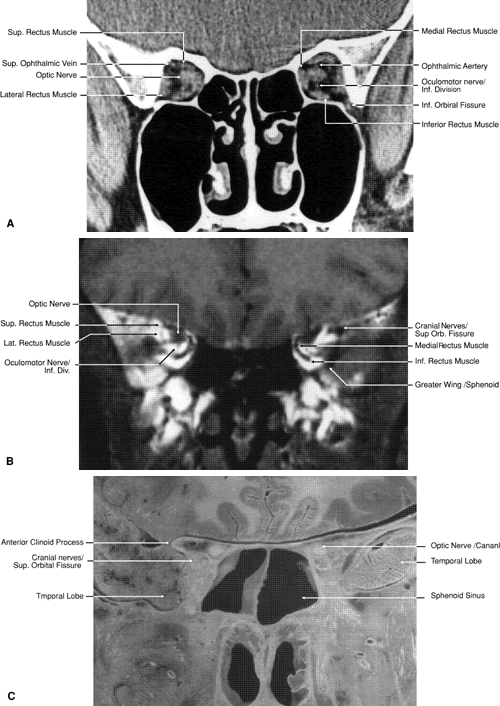

The globe is shown in Figure 12. The orbit and periorbital structures are shown in Figures 13 through 16, and the optic canal is shown in Figures 17 through 26. The cavernous sinus and optic chiasm are shown in Figures 27 and 28, and the posterior visual pathway and cranial nerves are shown in Figures 29 through 33.

ORBIT AND PERIORBITAL STRUCTURES

The bony orbital and periorbital anatomy is best visualized with CT, whereas the soft tissue anatomy can be visualized with either CT or MRI. The orbital cavities are roughly shaped like quadrilateral pyramids parallel to each other medially and lying on one side with their apex facing posteriorly. The widest portion of the orbit is approximately 1.5 cm posterior to the orbital rim (see Fig. 2). On average the adult orbit is 40 to 45 mm deep, with the anterior orbit measuring 40 mm wide and 35 mm high. The interorbital distance in the normal adult is 25 mm. In contrast, the newborn orbit is more rounded, with a width and height of 27 mm, and the orbit of a 7-year-old measures 28 mm high and 33 mm wide.48 The orbital volume is approximately 30 mL, in comparison to the globe, whose diameter of24 mm gives it a volume of 6.5 to 7.0 mL.

The full extent of the orbital roof and floor as well as the superior and inferior rectus muscles and the levator muscle is best evaluated using sagittal views of the orbit (see Figs. 17 through 20, 26). Reconstructed images are generally too crude to provide detailed imaging of these structures. Coronal views of the orbit are excellent for showing the vertical dimension of the lateral and medial orbital walls and the horizontal dimension of the orbital roof and floor. This view is also important for showing the cross-sectional areas of the globe and orbital soft tissue structures, including the muscles, nerves, vessels, and orbital fat.